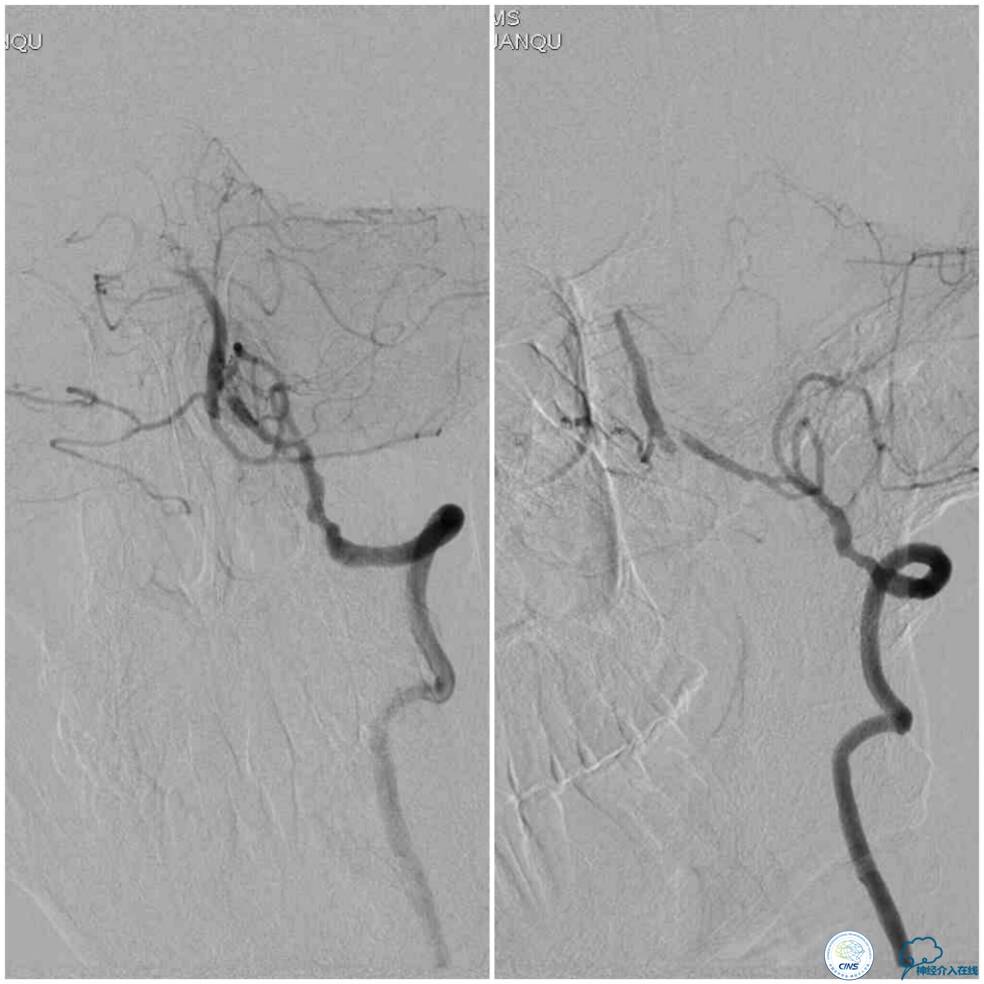

同期行DSA提示右椎动脉V4段发出右PICA后未见顺行显影(图2),左椎动脉V4段-基底动脉汇合处重度狭窄(图3),前循环向后循环的未见明显代偿(图4)。

图2

图3

图4